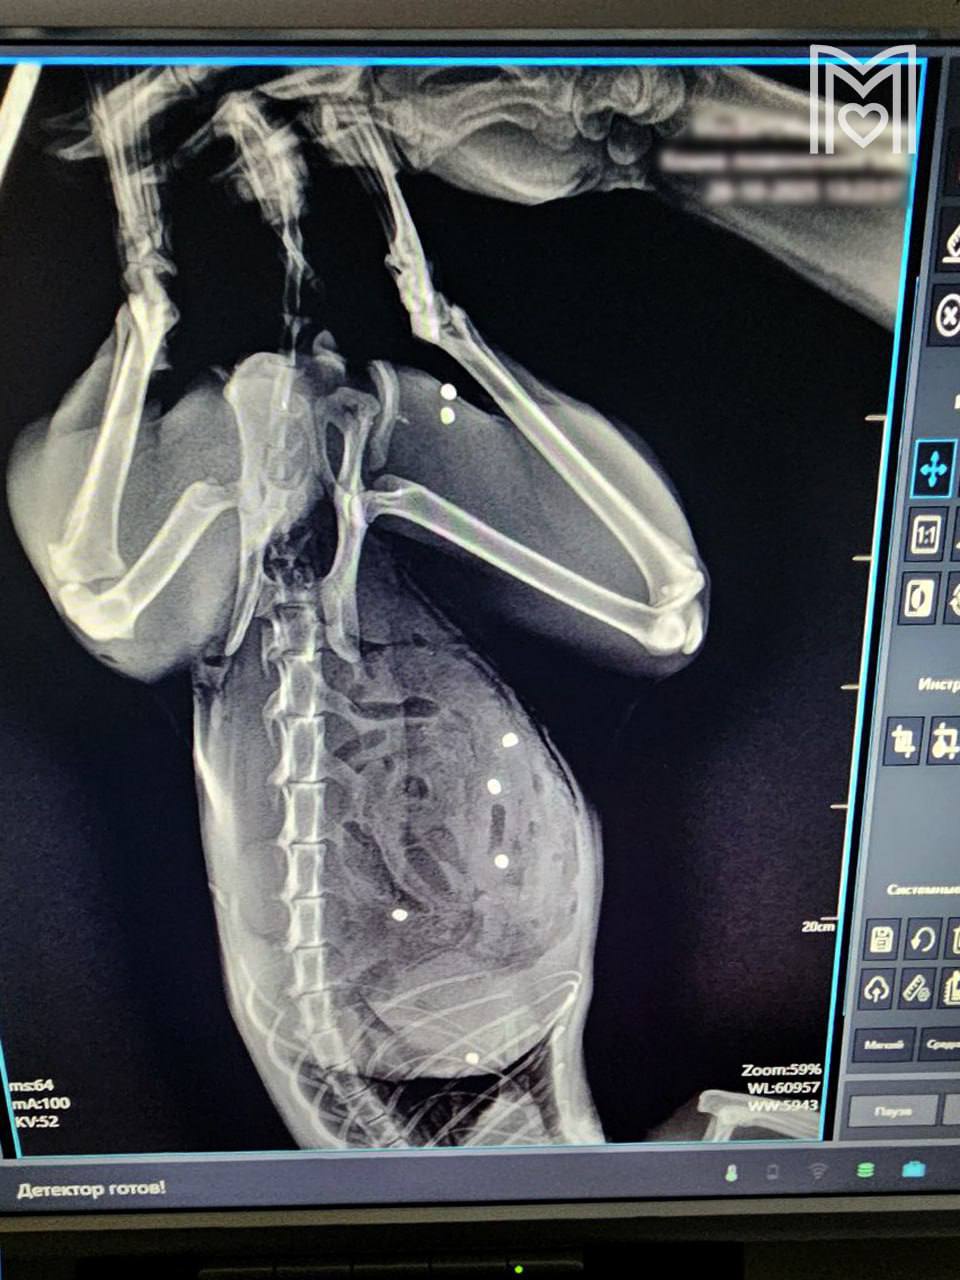

В Зеленограде ветеринары спасли кота Тимофея, у которого обнаружили десятки пулевых ранений: повреждён кишечник, селезёнка, а также грудная клетка и бедро. Операция длилась более трёх часов, и врачи смогли спасти питомца — сейчас его жизни ничего не угрожает. Москва 360°